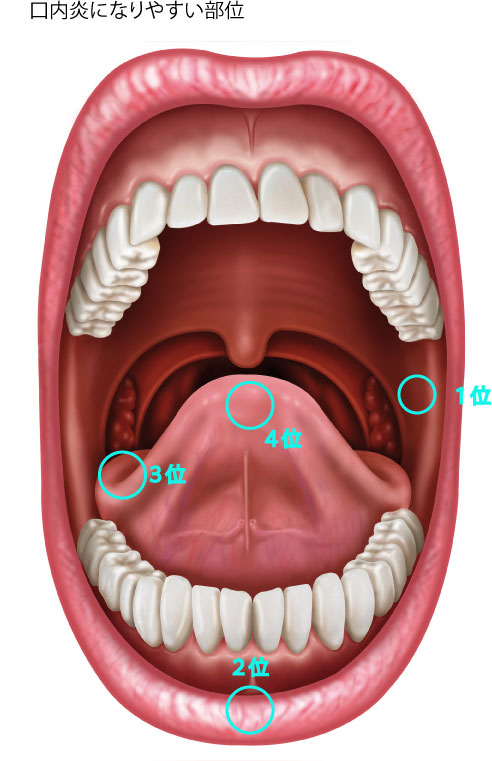

口内炎の原因・治し方大倉山駅前港北歯科クリニック。

知らぬ間に出来ている痛いヤツ!その名は「口内炎」豆知識京都市中京区の歯医者京都二条たけち歯科クリニック。

口内炎の原因と種類とは?できやすい場所・症状・早く治す方法や予防法を解説。

口内炎はなぜできるの?歯科衛生士ブログ港南台の歯医者 港南台パーク歯科クリニック。